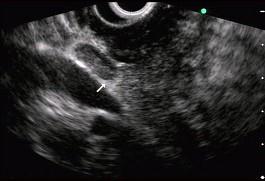

图中白色箭头所指可能诊断是 ( )A.胰腺占位B.肿大淋巴结C.血管影D.胆总管E.胆囊

选项 A.胰腺占位 B.肿大淋巴结 C.血管影 D.胆总管 E.胆囊

答案 B